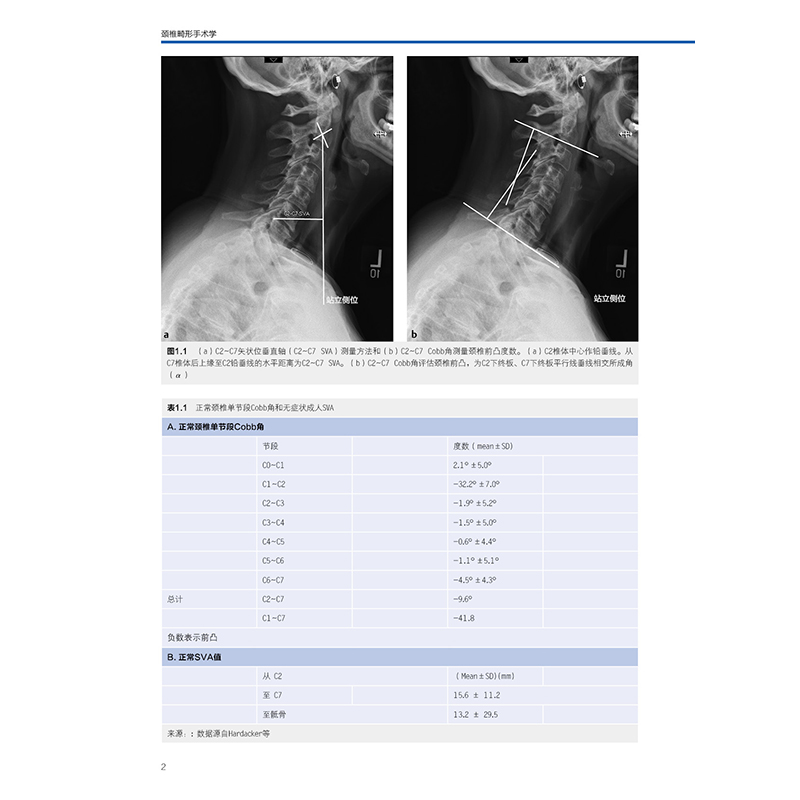

本书开篇介绍了颈椎畸形对健康显著影响的背景,以及临床和影像学评估的一般性知识。随后的章节详细描述了如何对颈椎畸形进行手术规划,包括截骨矫形的范围以及专家分享的手术细节。重要的是,多个章节重点介绍了手术的外科和内科并发症,并探讨了这些身体虚弱的患者接受手术治疗的风险分级。最后的几个章节则集中探讨了当前正在努力研究的有临床意义的颈椎畸形综合分型。从颈椎畸形的临床和影像学评估、分型,到不同部位、不同类型的截骨矫形技术,再到融合节段的选择以及围手术期的风险因素等,全面系统地归纳总结了近年来颈椎畸形领域的知识和理论,深入浅出、插图精美、形象生动,为读者献上了一份饕餮大餐,可以称作是目前颈椎畸形手术领域的经典著作。